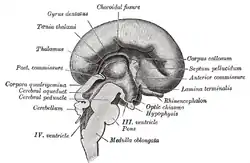

Median sagittal section of brain of human embryo of four months. (Lamina terminalis labeled at center right.) | |